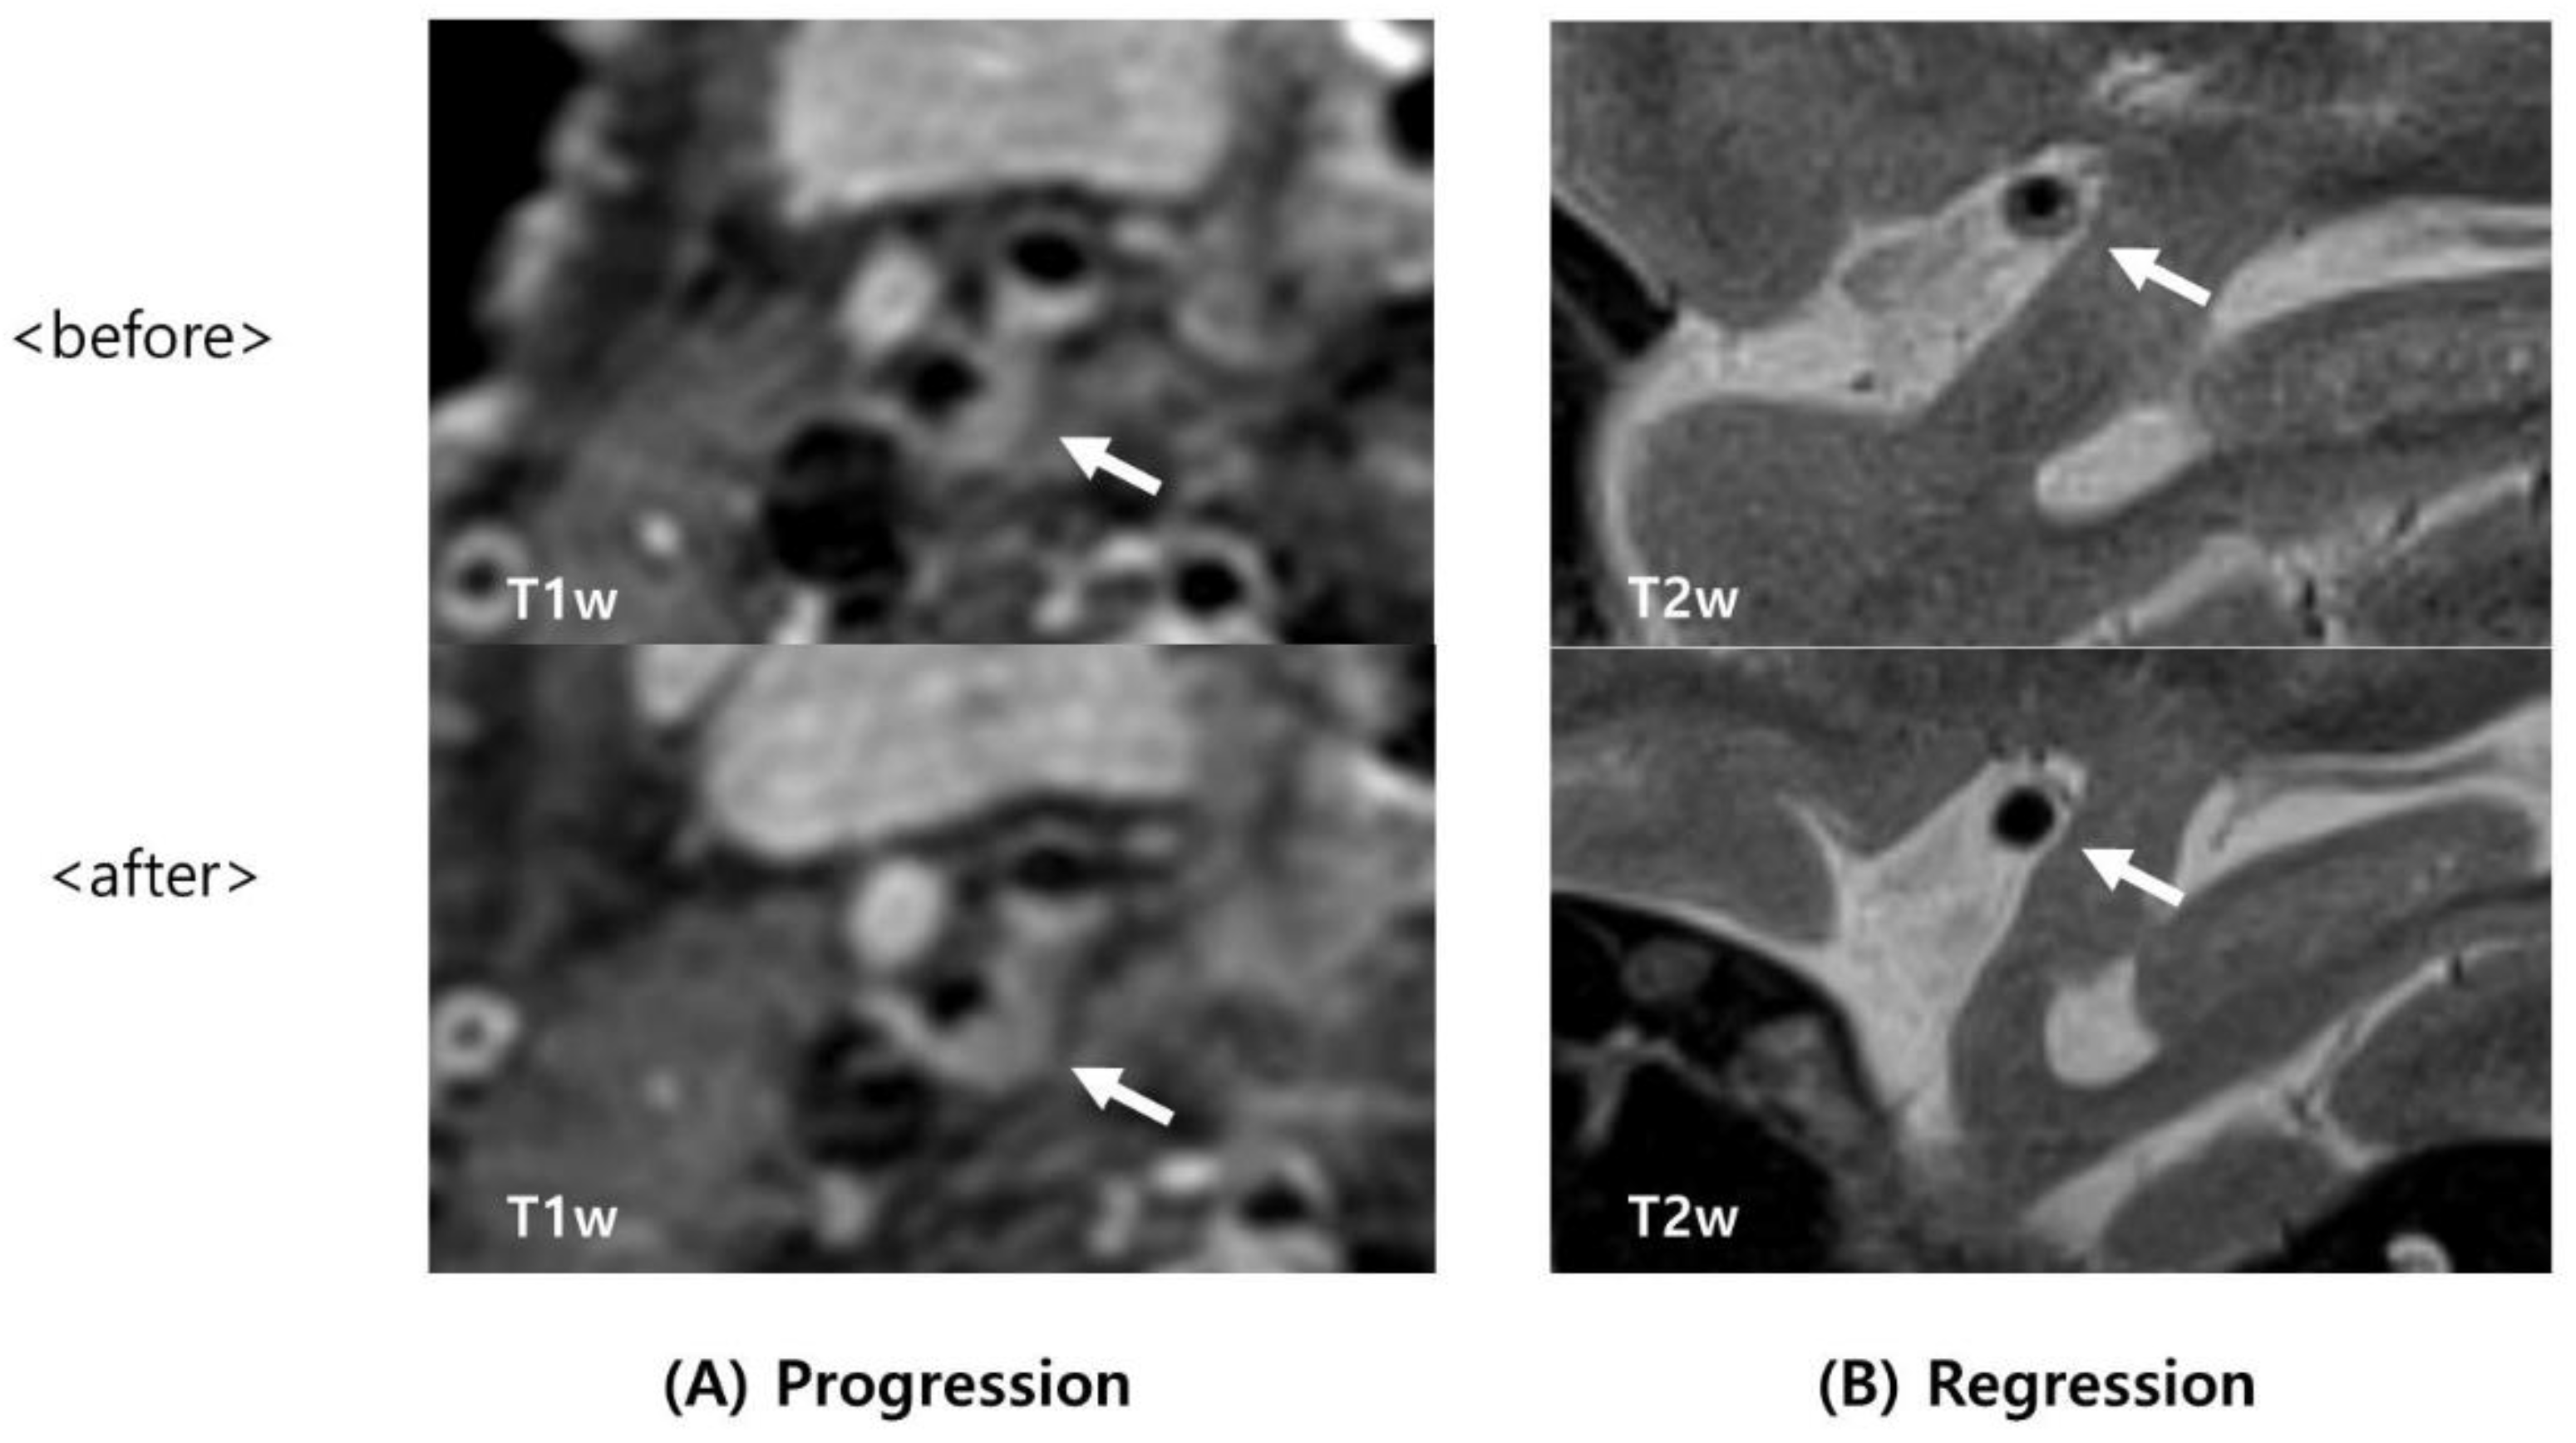

| Intraplaque hemorrhage (IPH) Regression of IPH | 14 (51.9) 3 (11.1) | 6 (40.0) 6 (40.0) | 0.461 0.029 |

| Regression of IPH | 5.33 (1.09–25.99) | 0.038 | 10.13 (1.31–78.57) | 0.027 |